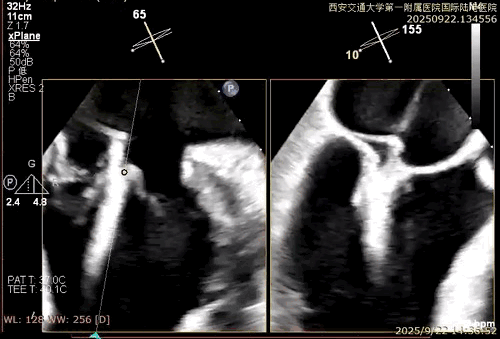

患者男性,69岁,术前TEE评估为FMR患者,因左室功能异常引发二尖瓣重度反流;后叶拴系,反流来源于整个2区,主要集中在2偏1、2偏3。患者瓣口面积约6.2cm²。房间隔可穿刺高度4.5cm。反流束宽度约19mm。AP径36.5mm。

术中在超声引导下完成房间隔穿刺,将第一枚XTR在左房内完成终定位,2偏3区完成植入,夹合效果良好,即刻超声显示轻微反流,完成夹子释放,手术效果良好,手术圆满结束,患者术后6小时即实现床旁活动。